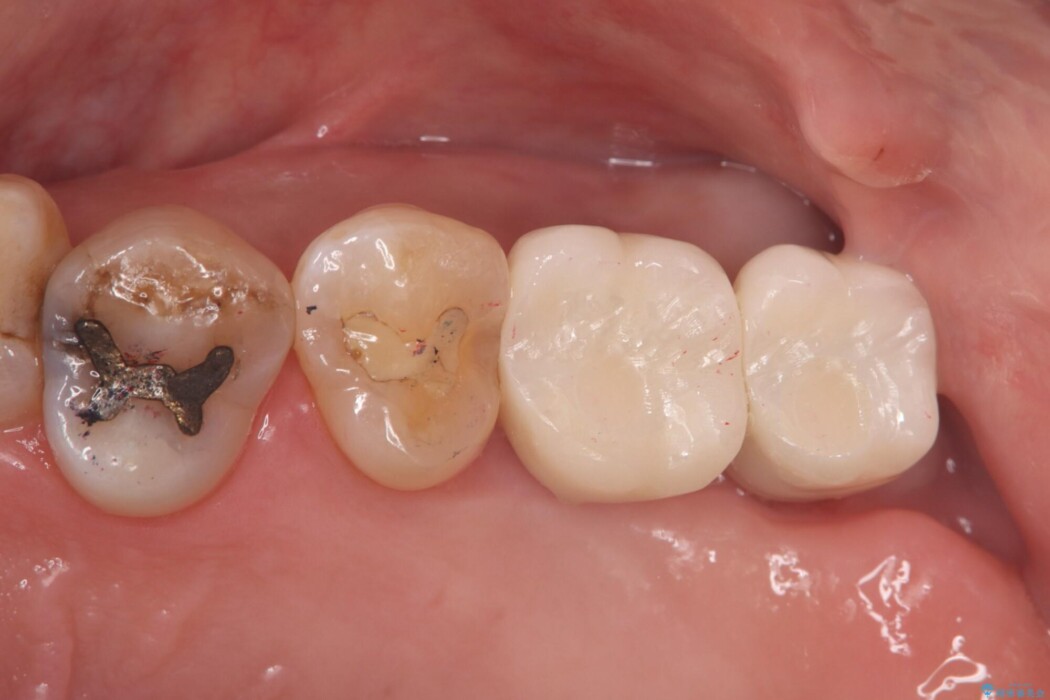

左上奥歯の欠損を、抜歯即時埋入を活用したインプラントで修復しました。

精密な位置決めと効率的な術式により、短期間でしっかり噛める喜びとお口全体の健康なバランスを取り戻すことができました。